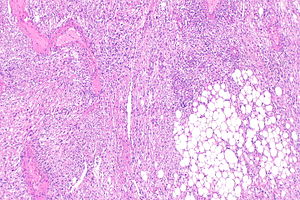

Epithelioid angiomyolipoma

Features:

- Carcinoma-like morphology.

- +/-Spindle cells.

- "High grade" nuclei.

- Pleomorphic nuclei.